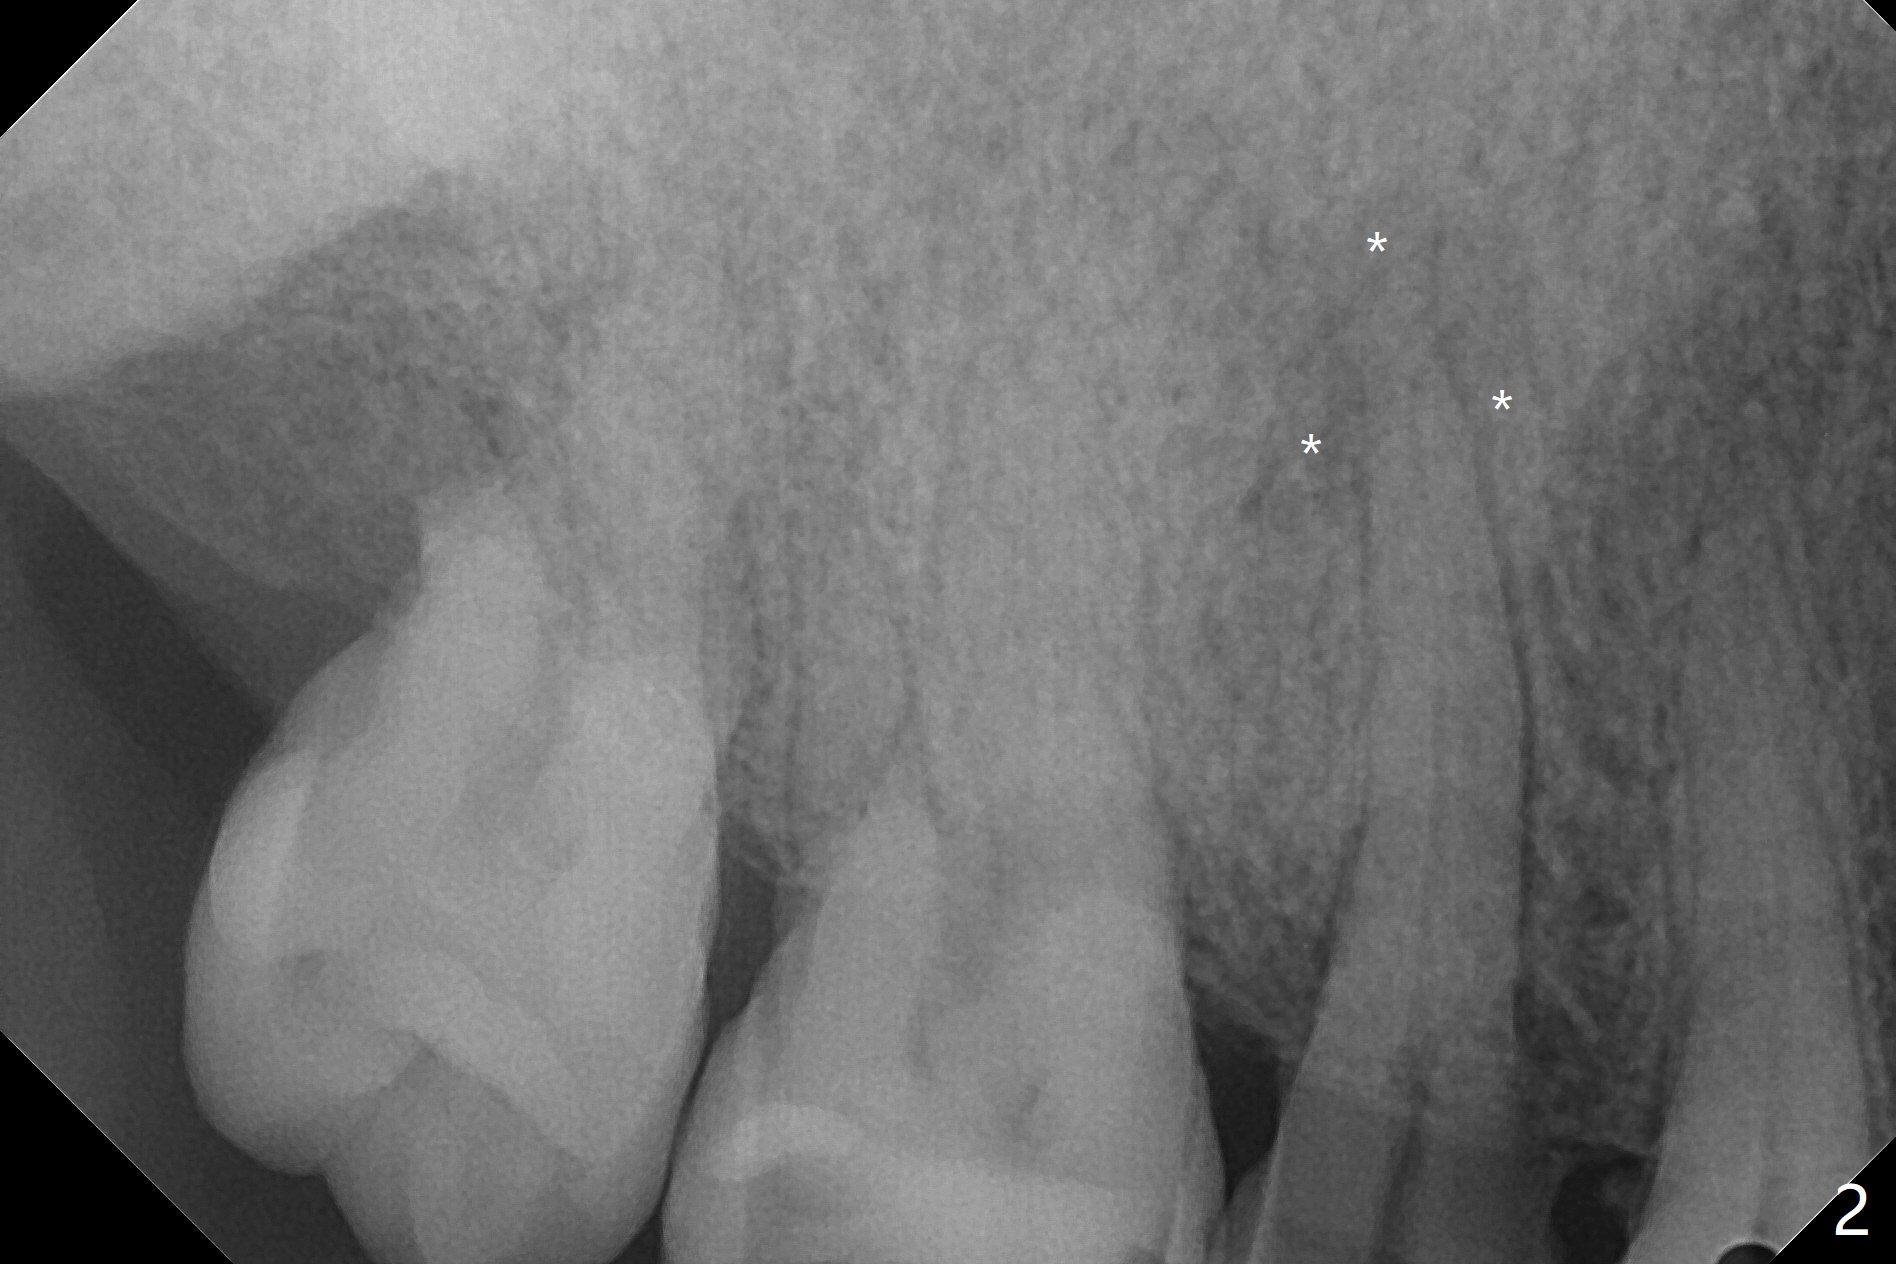

A 61-year-old man develops light pain associated with the tooth #4 with palatal subgingvial fracture (Fig.2 (*: periapical radiolucency)). Since the bone is apparent long (Fig.1), a long implant (15 mm bone level for guide, as long as 18 mm free hand or 20 mm tissue level) is to be placed for stability and early restoration. Because of palatal fracture in association with bone loss, the implant will be not placed too palatal. In fact the patient chooses to save the tooth with RCT.